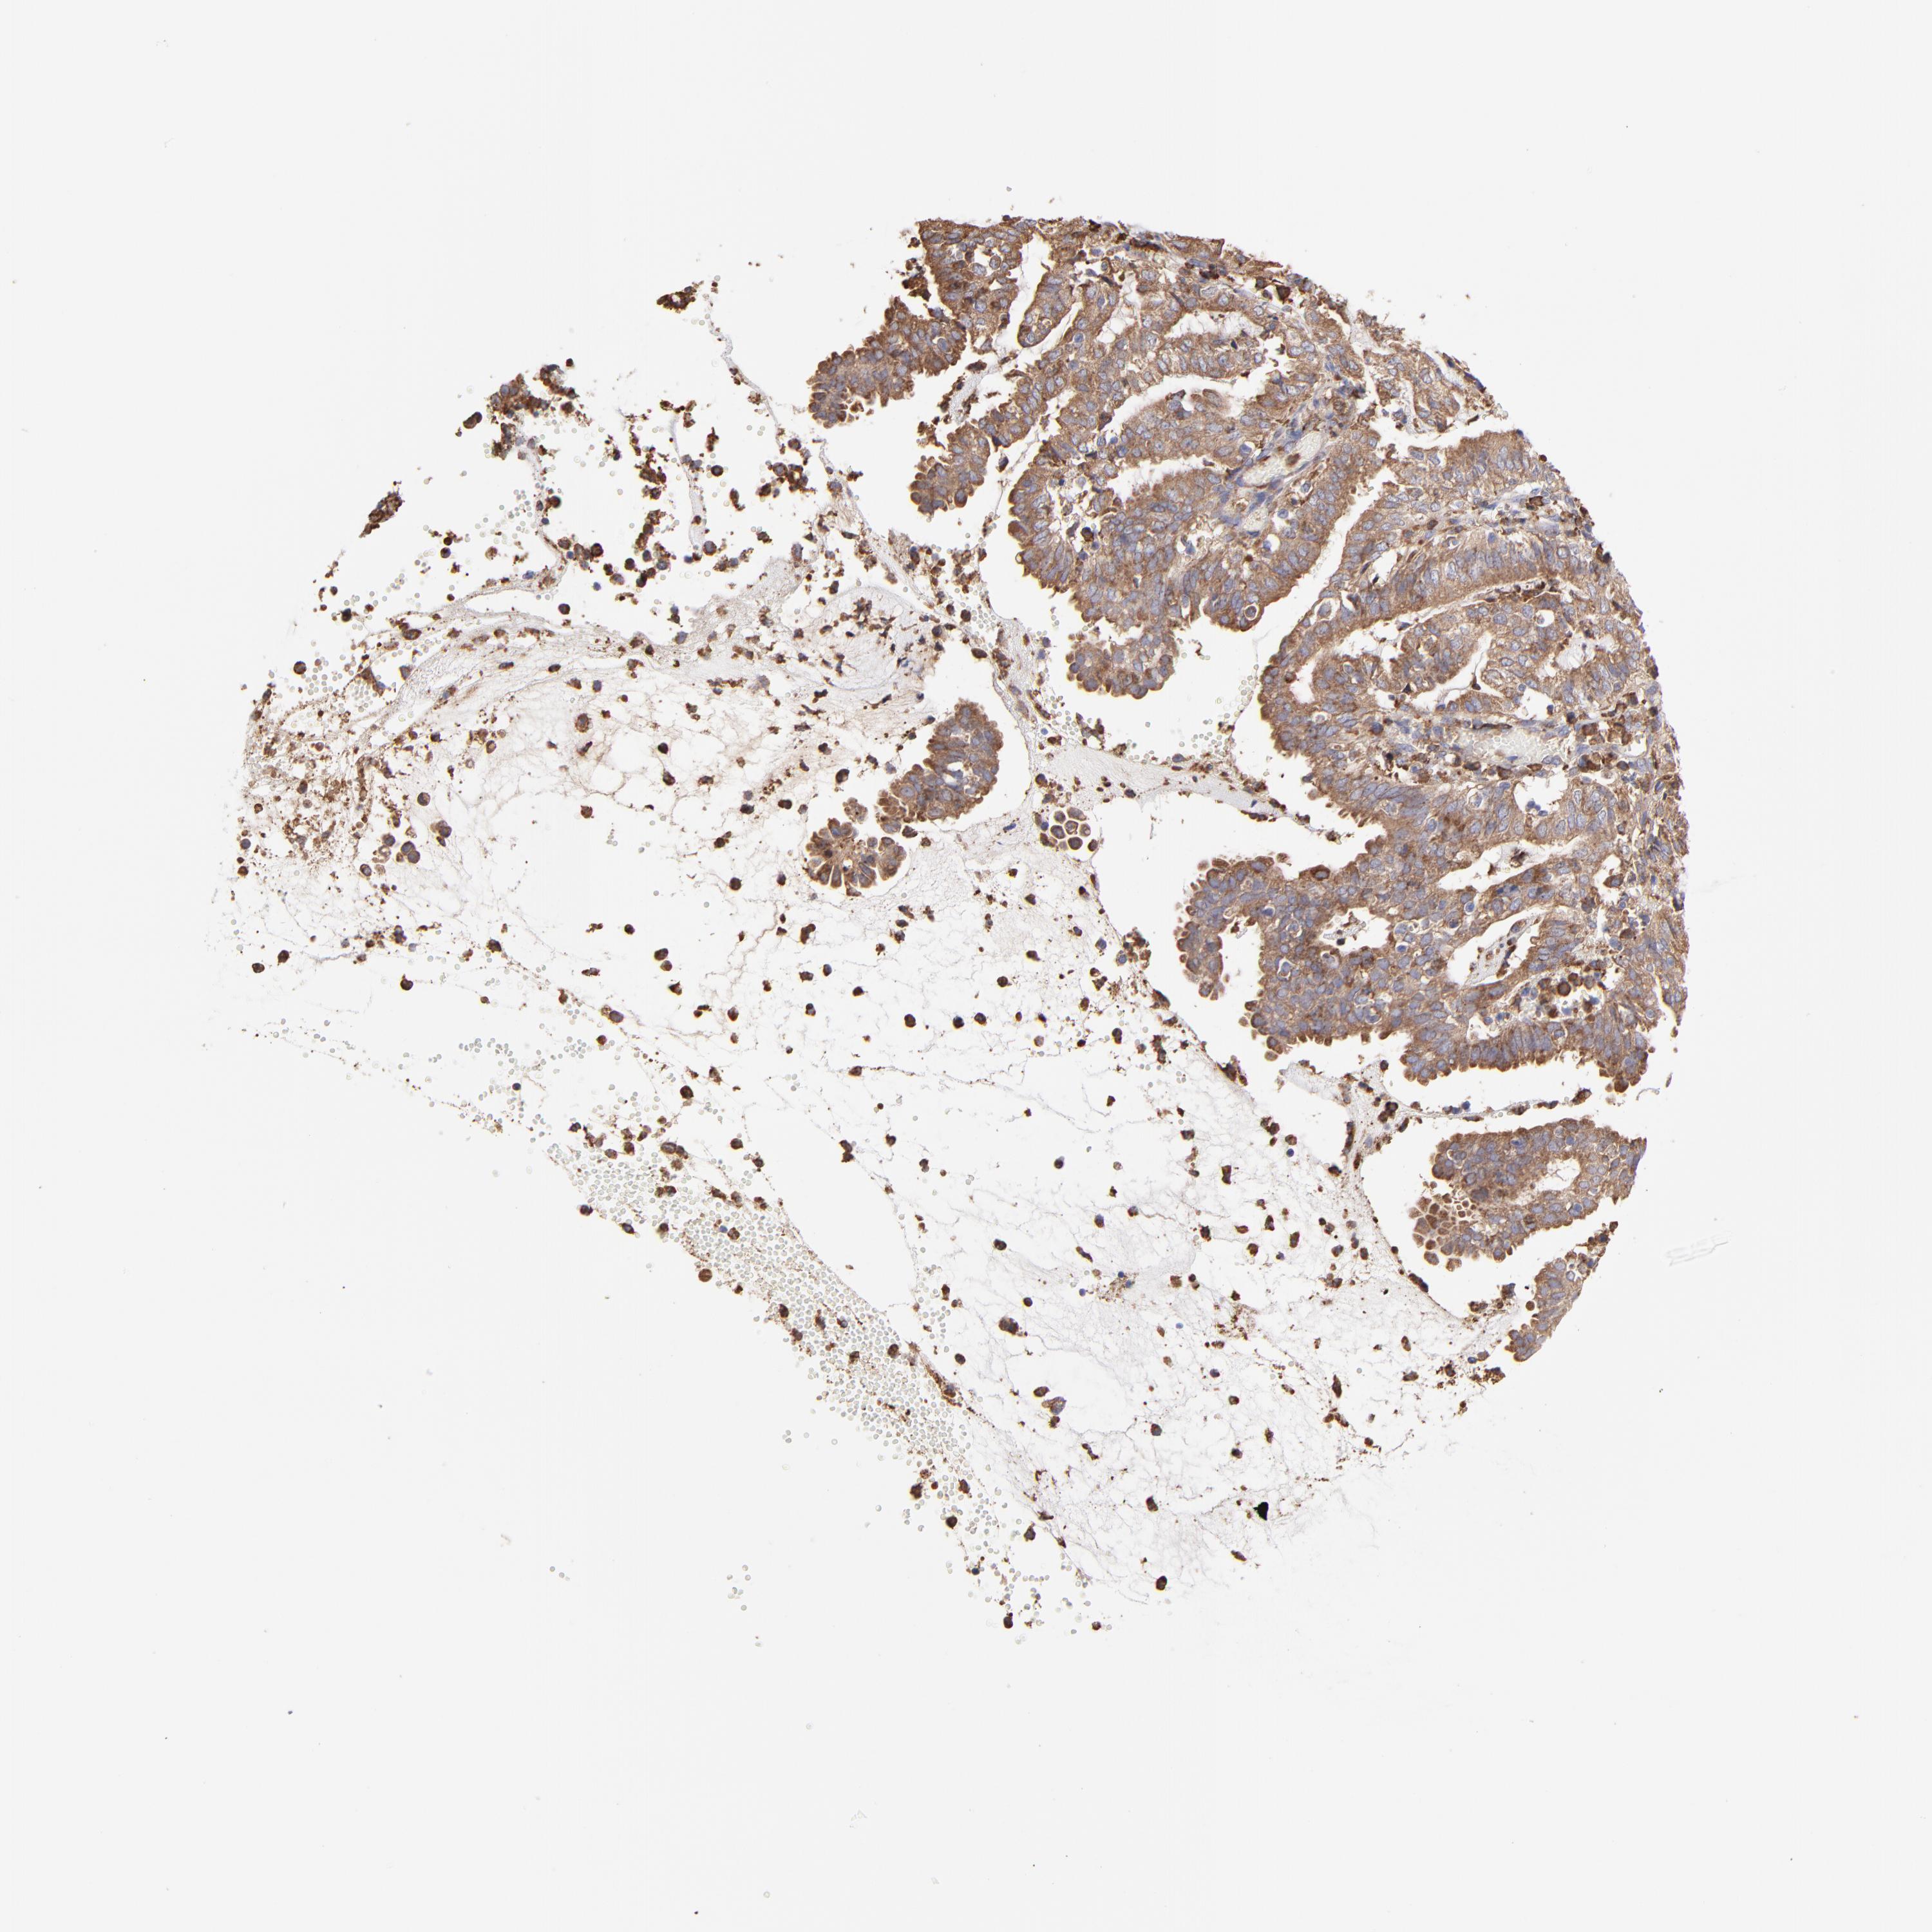

ENDOMETRIAL CANCER - Protein expressioni

A mouse-over function shows sample information and annotation data. Click on an image to view it in a full screen mode. Samples can be filtered based on level of antibody staining by selecting one or several of the following categories: high, medium, low and not detected. The assay and annotation is described here.

Note that samples used for immunohistochemistry by the Human Protein Atlas do not correspond to samples in the TCGA dataset.

Antibody stainingi

Antibody staining in the annotated cell types in the current human tissue is reported as not detected, low, medium, or high, based on conventional immunohistochemistry profiling in selected tissues. This score is based on the combination of the staining intensity and fraction of stained cells.

Each image is clickable and will lead to virtual microscopy that enables deeper exploration of all samples and also displays staining intensity scores, fraction scores and subcellular localization as well as patient and tissue information for each sample.

Antibody HPA002117

Staining

High

Medium

Low

Not detected

Intensity

Strong

Moderate

Weak

Negative

Quantity

>75%

75%-25%

<25%

None

Location

Nuclear

Cytoplasmic/membranous

Cytoplasmic/membranous,nuclear

Adenocarcinoma, NOS